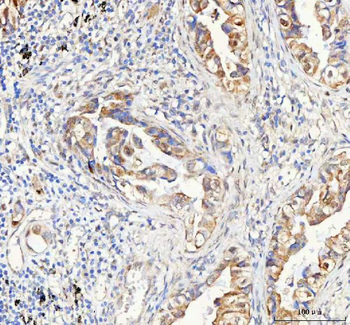

10 μg, 100 μgAnti-PAPSS2 Antibody [orb1743841]

ELISA, FC, IF, IHC, WB

Human, Mouse, Rat

Rabbit

Polyclonal

Unconjugated